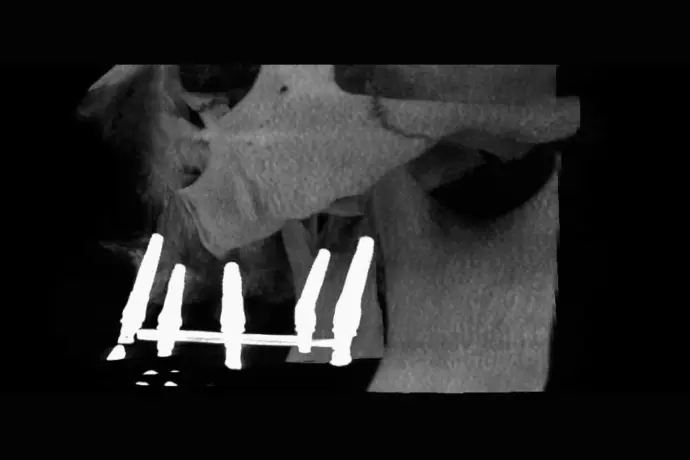

Référentiel Full Arch Club : All-on-4, All-on-X, palatal approach, trans-sinus, pterygoïdes, subpériostés personnalisés. Moins invasif, plus sûr.

• Chirurgie et mise en charge immédiate avec une approche sans greffes osseuse  et prédictible.

Opération chirurgicale en direct réalisée par le Dr Bernardo Nunes de Sousa